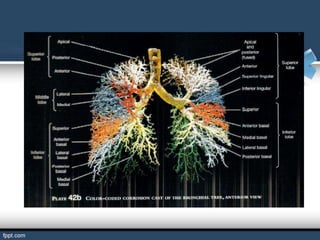

BRONQUIOS LOBARES

El bronquio principal derecho se divide en los llamados bronquios

lobares (son tres: superior, medio e inferior). El bronquio principal

izquierdo se divide a su vez en bronquios lobares (son dos: superior

e inferior).

Los bronquios lobares derecho e izquierdo se subdividen a su vez en

bronquios segmentarios o terciarios por cada lado.

BRONQUIOS SEGMENTARIOS

Son ramificaciones de los bronquios lobulares.

El hombre tiene 18 bronquios segmentarios que estos se ramifican

en bronquiolos.

Si los bronquios segmentarios ya no se puede subdividir se le llama

bronquiolo terminal.